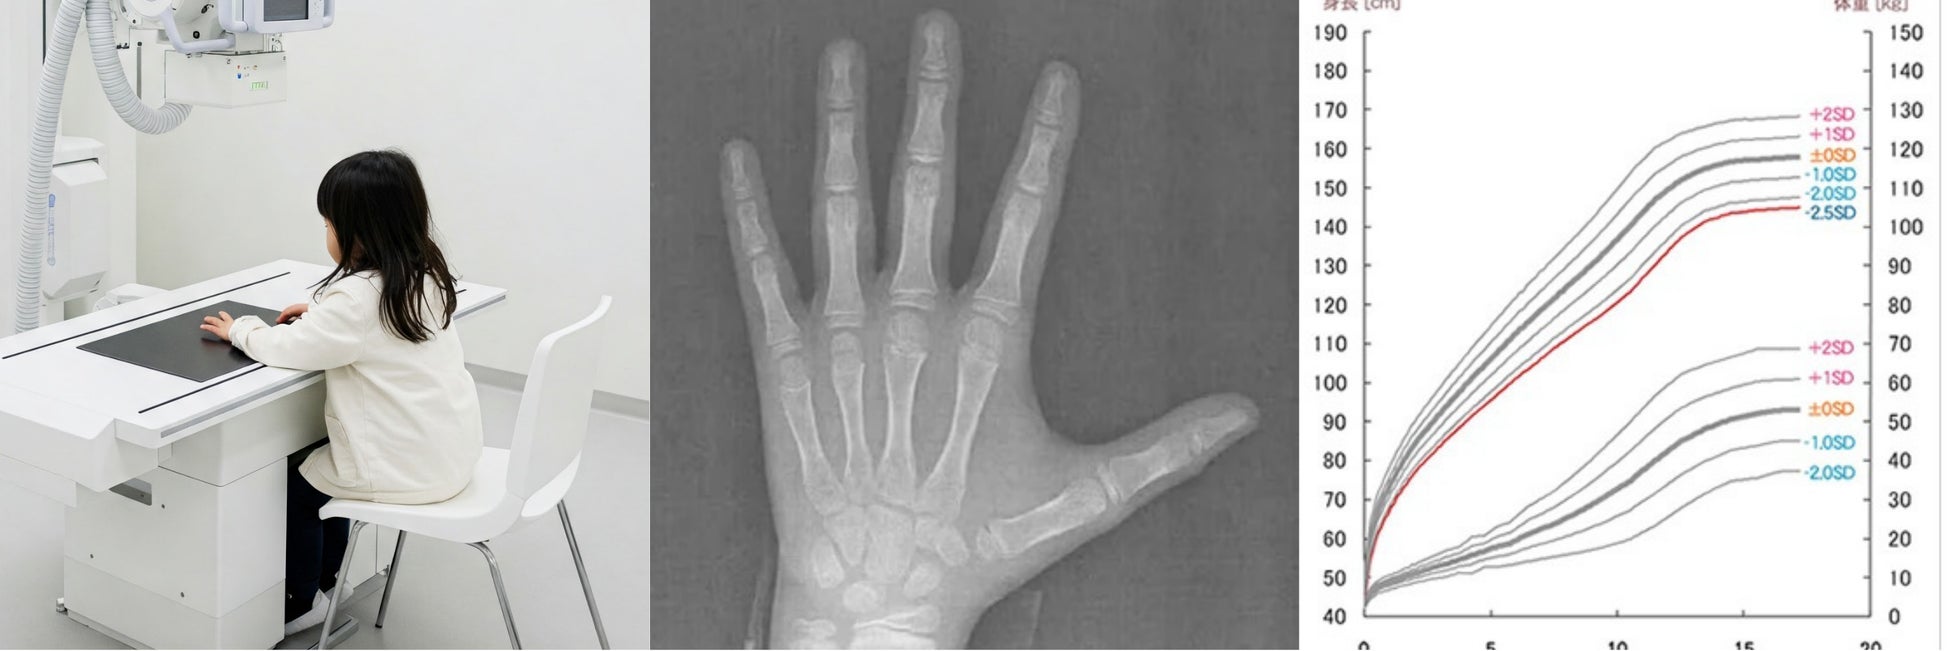

「あと+5cm」を叶えるための成長ホルモン治療。当院の身長予測シミュレーションは「現在のお子様の身長」や「ご両親の身長」といった基本的な情報に加え、レントゲンを用いた骨年齢の測定による、より精度の高い精密な身長予測が可能です。これらの情報をもとに、お子様の最終的な身長を予測し、医師より治療方針について丁寧にご説明いたします。